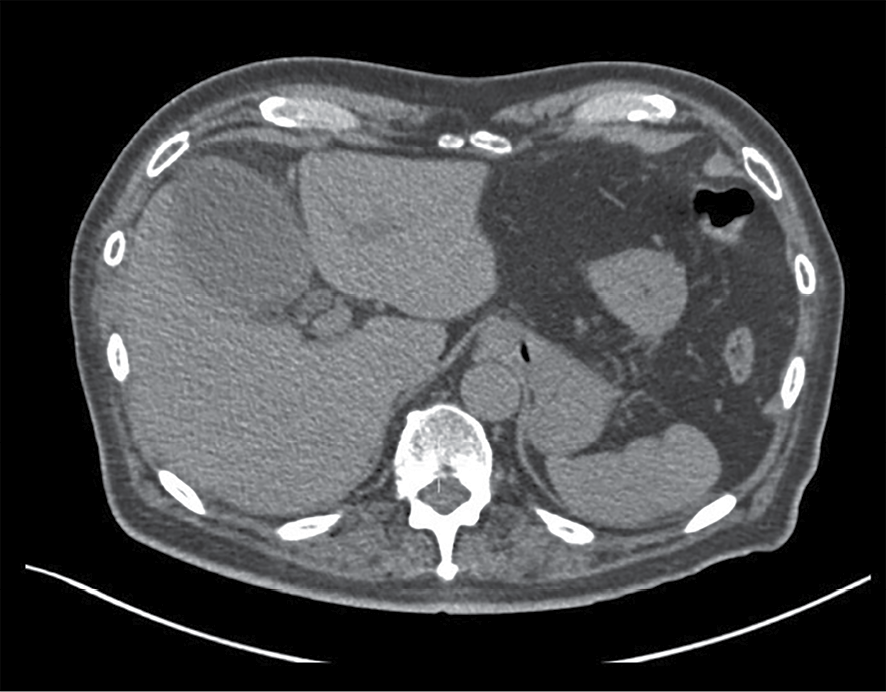

Paciente del sexo masculino de 87 años con dolor abdominal de 1 semana de evolución localizado en el mesogastrio, sin irradiación, escala visual analógica (EVA) 8/10; negó nausea, vomito o fiebre. Ingresó al servicio de urgencias, donde se solicitaron los estudios de imagen que se muestran en las figuras 1, 2 y 3.

2. En la figura 1, ¿cuáles son los hallazgos representativos que puedes observar?

a) Líquido libre en correderas.

b) Sin hallazgos de relevancia al padecimiento actual.

c) Hiperemia mural vesicular.

d) Engrosamiento mural vesicular.